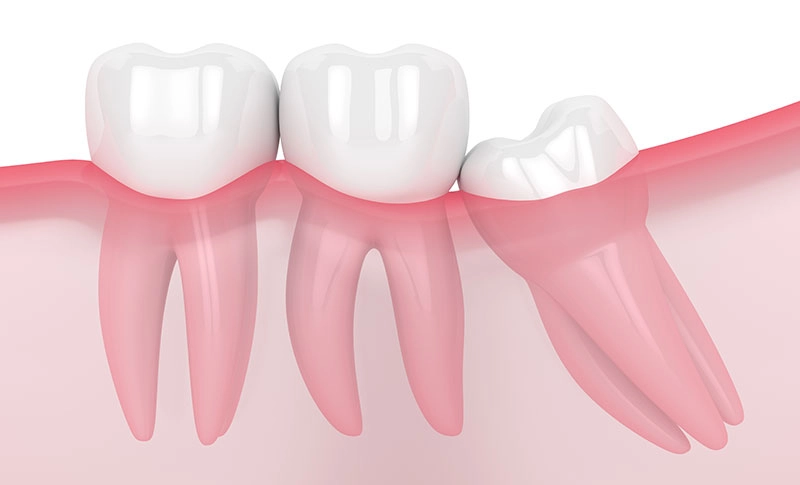

その結果、斜めに生えたり、一部だけ歯ぐきから顔を出したり、歯ぐきや骨の中に埋まったままになることがあります。

このような状態では、歯ぐきの腫れや痛み、隣の歯のむし歯、かみ合わせへの影響などを引き起こす場合があります。